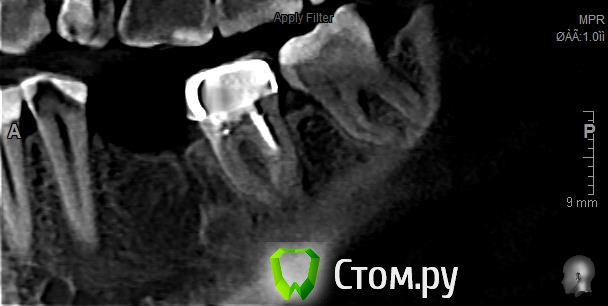

HSS Опубликовано 23 ноября, 2014 Поделиться Опубликовано 23 ноября, 2014 Добрый вечер, коллеги! При планировании имплантации в области 46 обнаружил неизвестное образование в области 46. На одной из проекций визуализируется, что-то наподобие свищевого хода в альвеолярном отростке, но на слизистой никаких изменений нет.Следовательно, вопрос, что это?Не будет ли проблем после установки имплантата? Ссылка на комментарий

kriokov Опубликовано 23 ноября, 2014 Поделиться Опубликовано 23 ноября, 2014 на остеому похоже, а на альвеолярном видимо кость так организовалась после удаления шестого Ссылка на комментарий

HSS Опубликовано 23 ноября, 2014 Автор Поделиться Опубликовано 23 ноября, 2014 на остеому похоже, а на альвеолярном видимо кость так организовалась после удаления шестогоЯ так понимаю, что остеома по соседству никакой опасности не несет, можно смело ставить? Ссылка на комментарий

zubnojvrach Опубликовано 26 ноября, 2014 Поделиться Опубликовано 26 ноября, 2014 я думал что это от резорцин-формалинового метода следы Ссылка на комментарий